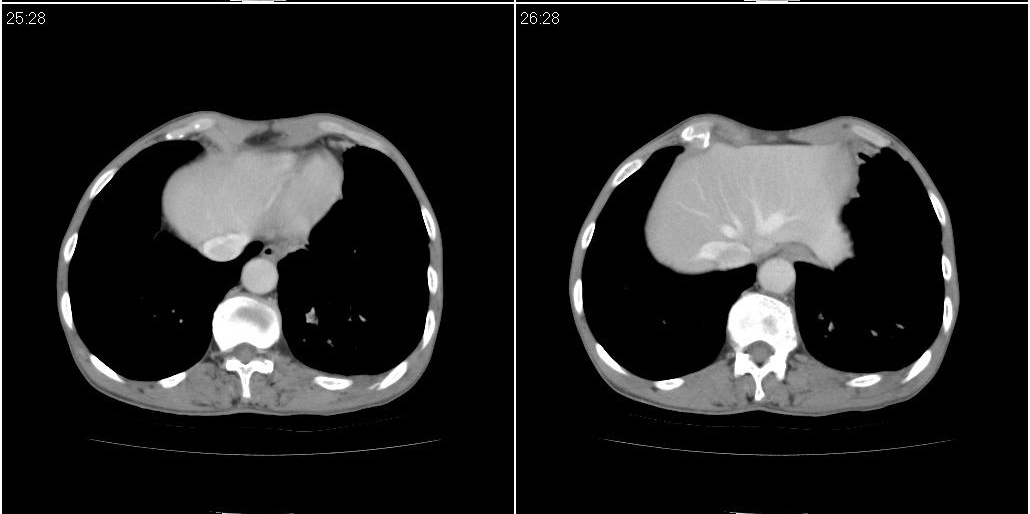

以下是ct检查的情况:

标题: ct增强:

[本贴已被 fanshl 于 2010-3-30 7:14:31 修改过]